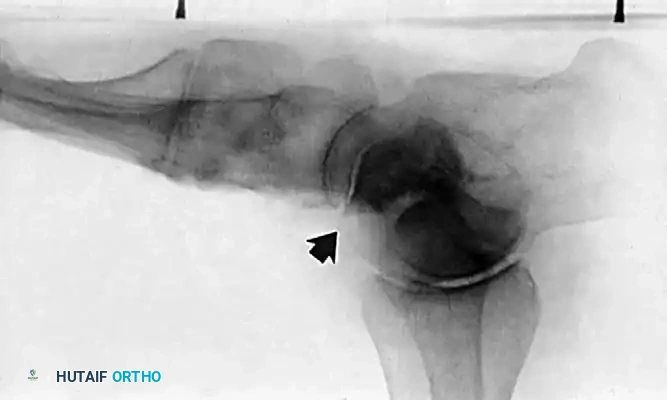

- Radiography: Degenerative arthritic changes are visible in the subtalar and/or talonavicular joints.

- Clinical Findings: Valgus tilt of the talus within the ankle mortise. The deformity involves not just the hindfoot, but the tibiotalar joint itself.